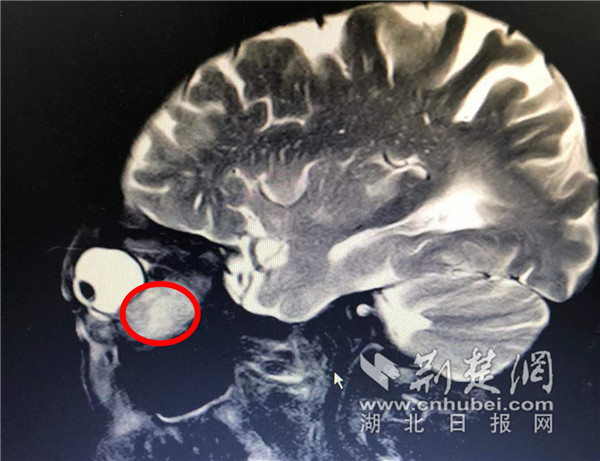

76岁的刘爹爹在2个多月前,突然感觉左眼疼痛,有异物感,还出现了畏光、流泪、视物有重影的情况,左眼往外突出的情况也越来越明显,还偶尔伴有头疼,家人以为他这是甲亢所致。近日,爹爹自觉症状越来越严重,家人便带他来到武汉市中心医院后湖院区眼科就医。接诊的副主任医师姚骏对刘爹爹进行检查,发现爹爹的左眼眼球基本无法转动,根据经验判断是眼眶内有肿物挤压所致。经过后续的相关检查,证实了爹爹左眼眼眶里眼球的后下方有一个约眼球相同大小的肿物。

刘爹爹眼眶内的肿瘤与眼球体积相当。通讯员供图